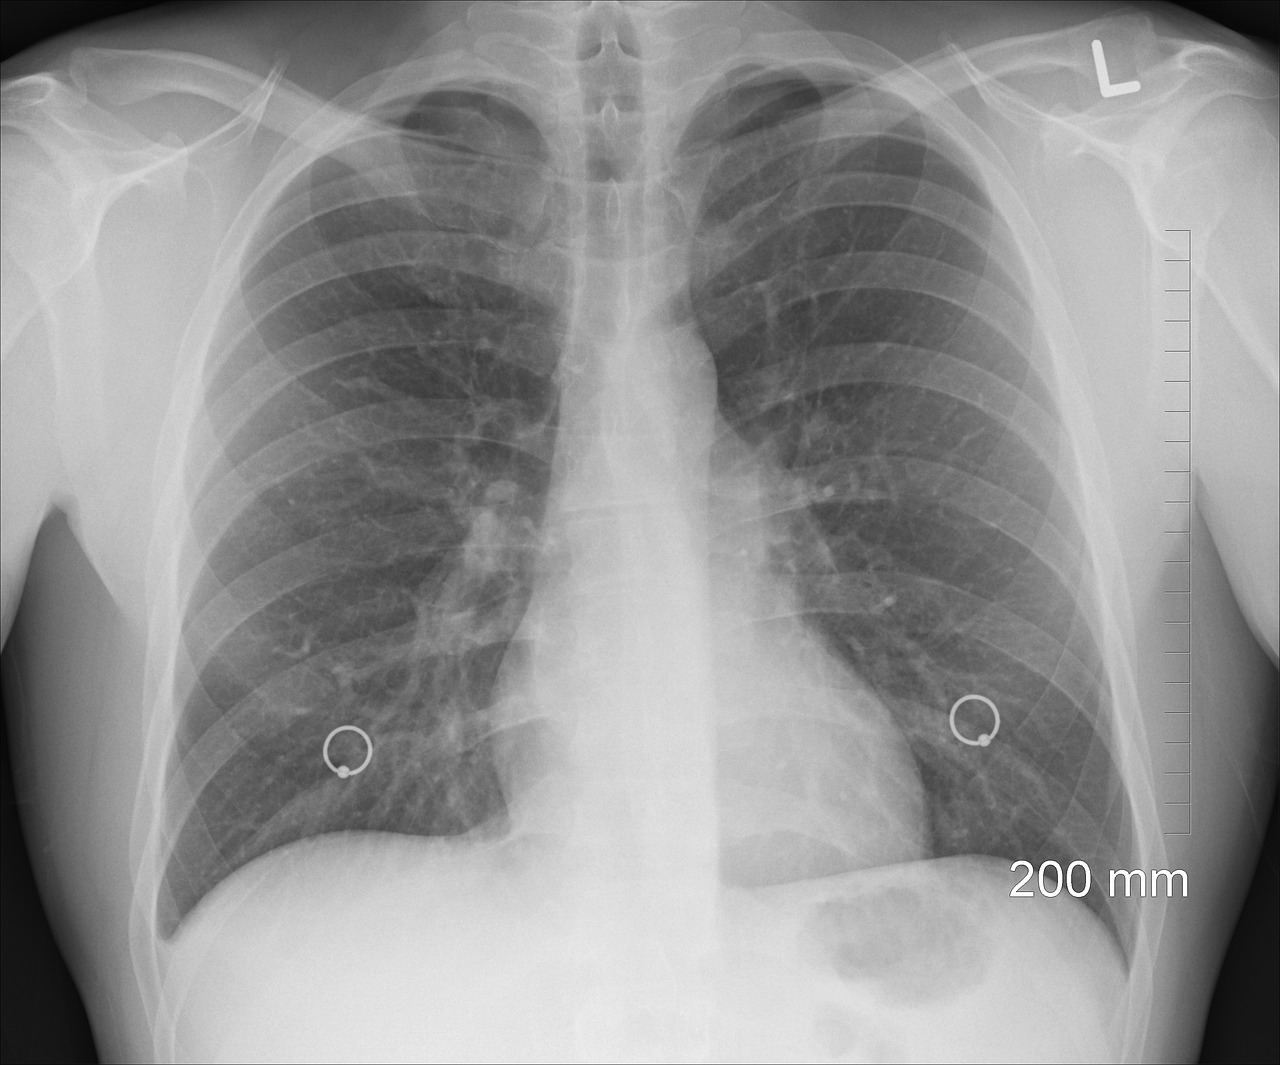

2️⃣ 늑막염 🫁 (폐를 감싸는 막에 염증이 생긴 상태)

- 기흉(폐에 공기가 찬 상태)

- 깊게 숨을 들이마시거나 기침할 때 옆구리가 찌릿하게 아픔

- 호흡이 어려워지고 숨이 차는 느낌이 듦

고열이 동반되거나 호흡곤란이 있다면 반드시 병원 방문! 🚑